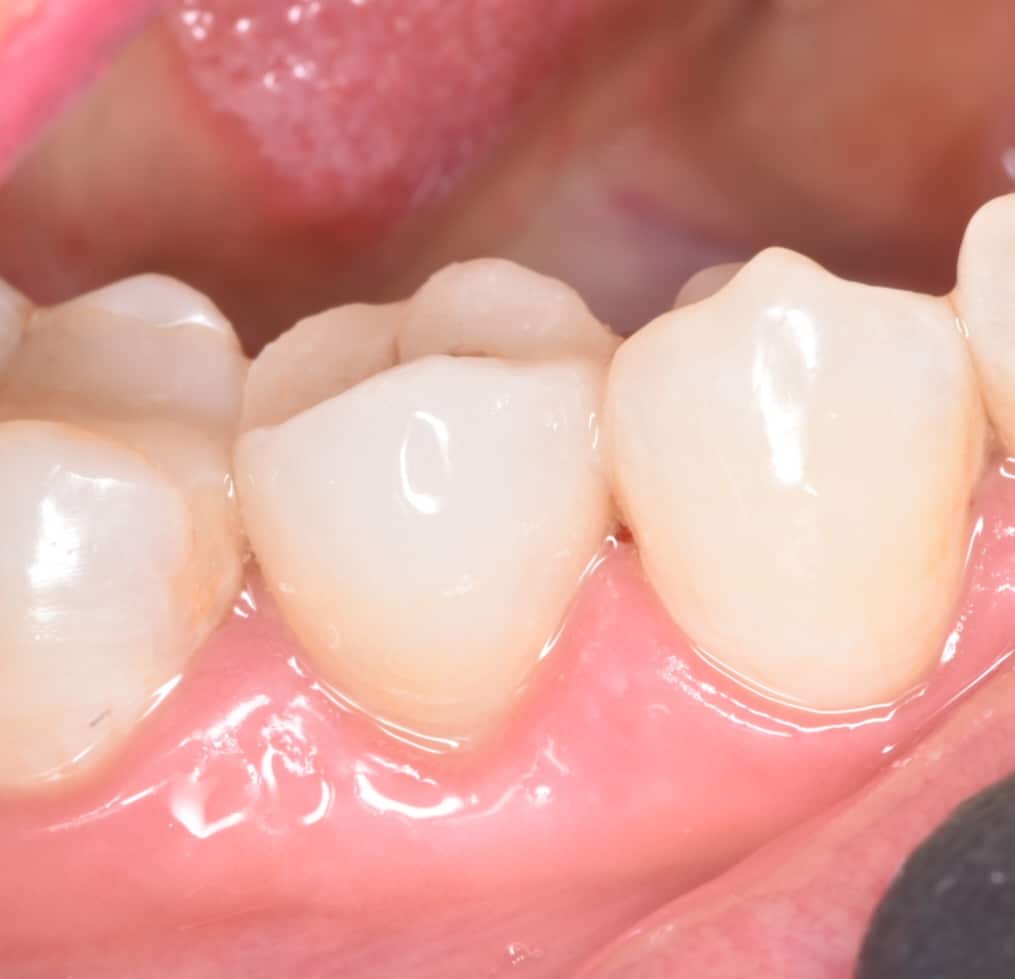

Initial situation showing badly carious lower second premolar

Buccal view showing the same destruction of the tooth, the patient insisted on restoring her tooth

One year follow-up, healthy , functional and durable